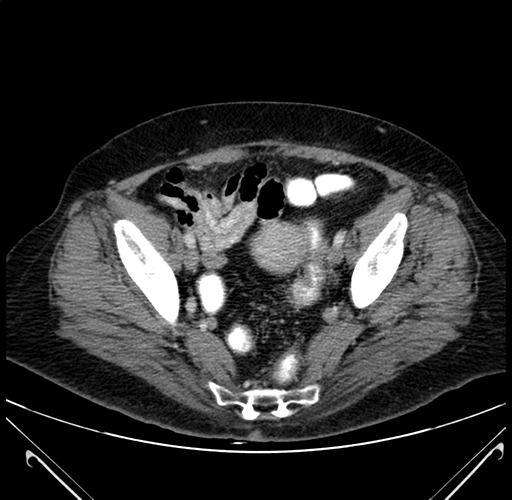

Pre-Chemo: Axial Venous

Axial Venous